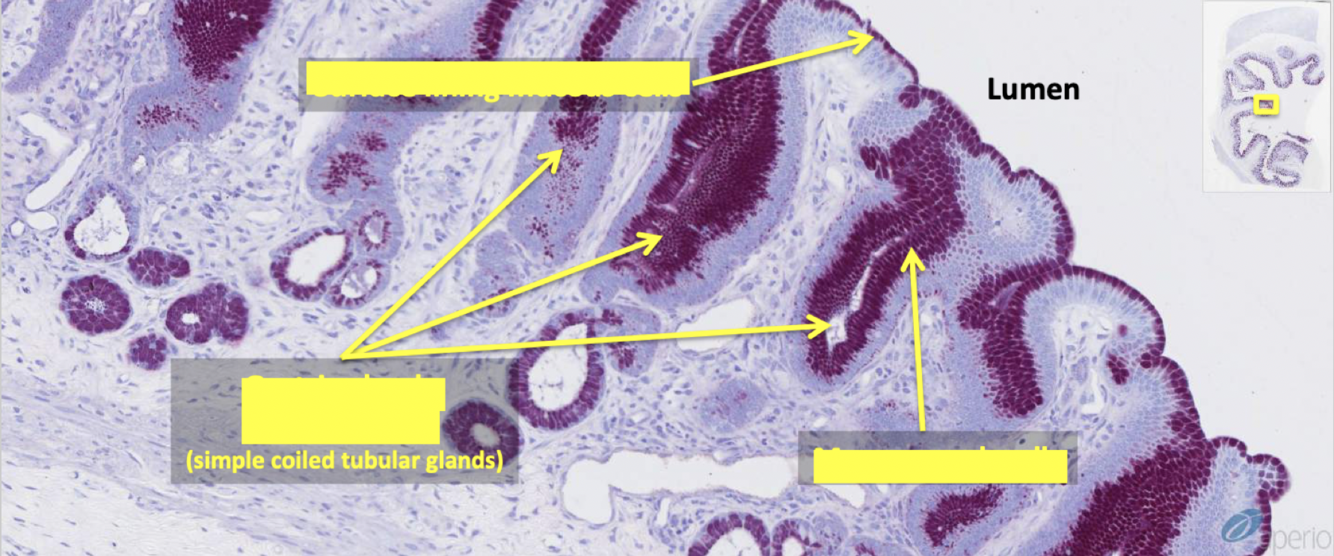

purpose of brunner’s glands

produce sodium bicarb and neutralizing compounds